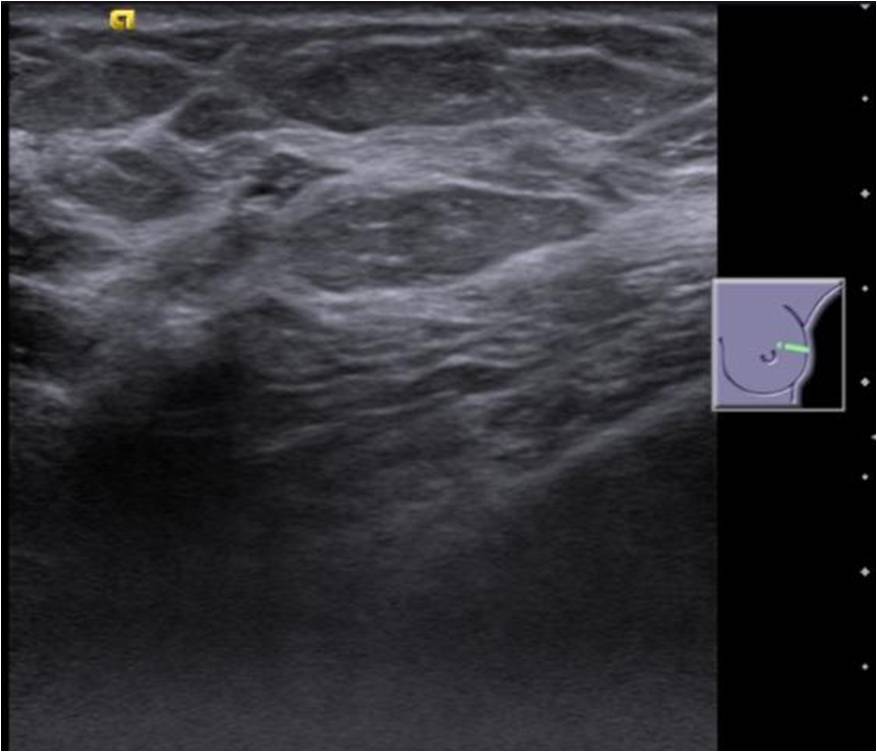

An asymptomatic 49-year old lady underwent a screening mammogram [Figure 1.]. In a background of heterogeneously dense breast parenchyma there was a 10mm round mass in the upper-outer quadrant of the left breast (anterior-third) with obscured posterior margins. No calcifications, spiculated mass or significant axillary lymph nodes were noted. She was recalled for further clinical assessment which revealed a palpable lump and an ultrasound (US) was advised. Sonomammogram [Figure 2.], in the area of mammographic abnormality, revealed a 12 x 10mm thick walled cyst with a 2mm polypoidal echogenic mural nodule arising from it’s non dependant wall. No other focal abnormality was seen in the rest of the left breast. Mildly enlarged nodes with slightly thickened cortex were noted in the left axilla. Ultrasound-guided biopsy of the complex cyst was performed [Figure 3.] with no complications. Histopathology [Figure 4] revealed larva of the cysticercal parasite (racemose cyst wall) with a surrounding giant cell reaction. Clinical follow-up after a two-month course of albendazole showed no palpable abnormality and USG [Figure 5.] in the region of abnormality showed resolution of the cyst.